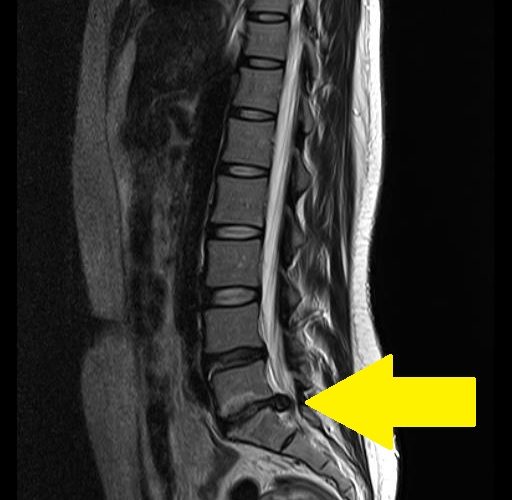

病院に行き、MRIを撮ったところL5とS1間の椎間板が破裂していました。

病院では、基本的に治療法はない、おまけに一生付き合わなければならないようなことを言われ、椎間板は再生しないとも言われました。病院でできることとしては、鎮痛のためのステロイド注射か、手術しかないというのが、全ての一般病院が締め合わせたような返答でした。

一時あまりに痛み、生活にも支障があったので、手術も考慮に入れ外科医と面接をすると、外科医は僕のMRIを見ながら、「椎間板が破裂して散っているよ。よく平気な顔で立って歩いているね」と驚いた顔で僕に言ったものです。